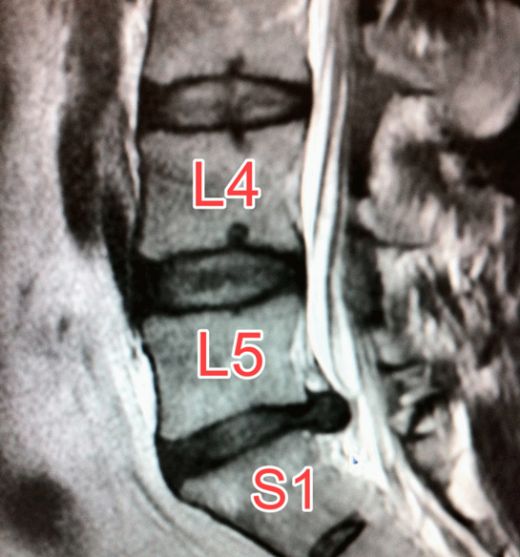

Bel Fıtığı MR Kullanımı ve Faydaları Nelerdir?Bel fıtığı, omurgayı oluşturan disklerin yerinden kayması veya hasar görmesi sonucu meydana gelen bir sağlık problemidir. Bu durum, sinir köklerine ve omuriliğe baskı yaparak çeşitli ağrı, uyuşma ve güçsüzlük gibi belirtilere neden olabilir. Bel fıtığı tanısında ve tedavi sürecinin planlanmasında manyetik rezonans görüntüleme (MR) yöntemi sıklıkla kullanılmaktadır. Bu makalede, bel fıtığı MR kullanımının ne olduğu, nasıl yapıldığı ve ne gibi faydalar sağladığı üzerinde durulacaktır. Bel Fıtığı Nedir?Bel fıtığı, omurganın alt kısmındaki disklerin yıpranması veya yırtılmasıyla oluşan bir durumdur. Diskler, omurga arasında sünger benzeri yapılar olarak görev yapar ve hareket esnasında şok emici özellikleri ile omurlar arasındaki boşluğu doldururlar. Fıtıklaşma, bu disklerin dış kısmının yırtılması ve iç kısımdaki jel benzeri maddenin dışarı sızması ile gerçekleşir. Bu durum, çevredeki sinir köklerine baskı yaparak ağrılara ve diğer semptomlara yol açabilir. MR Nedir ve Nasıl Çalışır?Manyetik rezonans görüntüleme (MR), vücudun iç yapılarının yüksek çözünürlüklü görüntülerini elde etmek için kullanılan bir görüntüleme tekniğidir. MR cihazı, güçlü bir manyetik alan ve radyo dalgaları kullanarak vücudun iç yapılarındaki protonların hareketini izler ve bu bilgiler sayesinde detaylı görüntüler oluşturur. MR, özellikle yumuşak dokuların, sinirlerin ve disklerin değerlendirilmesinde oldukça etkilidir. Bel Fıtığı MR Kullanımının Faydaları Bel fıtığı tanısında MR kullanımının birçok avantajı bulunmaktadır:

Sonuç Bel fıtığı, yaşam kalitesini olumsuz etkileyen önemli bir sağlık sorunudur. Manyetik rezonans görüntüleme, bel fıtığının tanısında ve tedavi planlamasında büyük önem taşımaktadır. Yüksek çözünürlük sunması, radyasyon içermemesi ve detaylı inceleme imkanı sağlaması gibi avantajları ile MR, bel fıtığı hastalarının tedavi süreçlerinde vazgeçilmez bir araçtır. Ekstra Bilgiler Bel fıtığı MR kullanımı, hastaların durumunun doğru bir şekilde değerlendirilmesi ve etkili bir tedavi planının oluşturulması açısından önemli bir rol oynamaktadır. Bu nedenle, bel fıtığı belirtileri gösteren bireylerin bir sağlık uzmanına başvurarak gerekli görüntüleme testlerini yaptırmaları önerilmektedir. |